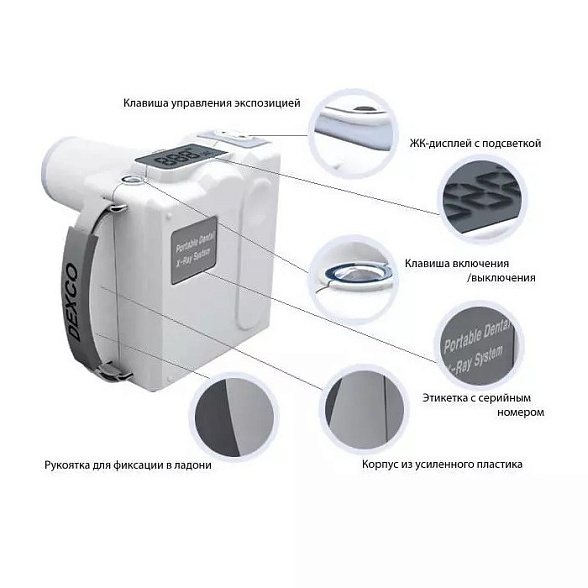

Satelec X-Mind DC Mobile - высокочастотный мобильный дентальный рентгеновский аппарат (Франция)

Satelec X-Mind DC Mobile: Мобильный рентген для современной стоматологии

Высокочастотный ментальный рентгеновский аппарат Satelec X-Mind DC Mobile — это воплощение французского качества и инноваций в компактном и автономном формате. Разработанный для клиник, где важны мобильность, скорость работы и бескомпромиссное качество снимков, этот аппарат становится надежным партнером в ежедневной диагностической практике.

Главное преимущество Satelec X-Mind DC Mobile — полная свобода перемещения. Аппарат не привязан к конкретному кабинету, что позволяет проводить рентгенографию у кресла пациента, в хирургическом или ортопедическом отделении, максимально оперативно получая необходимую диагностическую информацию.

- Исключительная мобильность: Прочная конструкция на колесах с системой блокировки позволяет легко и безопасно перемещать аппарат между кабинетами. Вы экономите время на организации процесса и не привязываете диагностику к одному помещению.

- Автономность и готовность к работе: Встроенный аккумулятор позволяет аппарату работать без подключения к сети, что особенно ценно в условиях перебоев с электричеством или при необходимости сделать снимок в нестандартном месте.

- Простота и интуитивность управления: Эргономичная панель управления с понятным интерфейсом и цифровым дисплеем минимизирует время на обучение и снижает риск ошибок. Настройка параметров занимает секунды.

- Надежность и долговечность: Бренд Satelec (Acteon Group) — синоним качества в стоматологическом оборудовании. Аппарат создан для интенсивной ежедневной эксплуатации в условиях клиники.